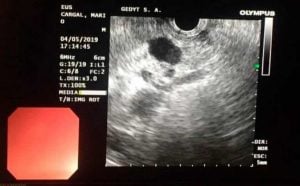

Un hecho de singular relevancia en el ámbito de la salud local, y con una importancia que trasciende Trenque Lauquen, el servicio de Gastroenterología del Hospital Municipal realizó la primera ecoendoscopía lineal con punción de una lesión orgánica de páncreas y la posterior colocación de una prótesis biliar autoexpansible.

Y precisaron que bajo anestesia general, un equipo médico coordinado por el doctor Ignacio Yarza hizo la ecoendoscopía lineal con punción y confirmación de obtención de material para examen anatomapatológico intra-procedimiento, habiendo un patólogo en la sala.

Una vez concluido ese procedimiento, se realizó el drenaje endoscópico de la vía biliar a través de la colocación de una prótesis biliar autoexpansible parcialmente cubierta. La paciente presentó buena evolución, con alta de internación a las 24 horas.